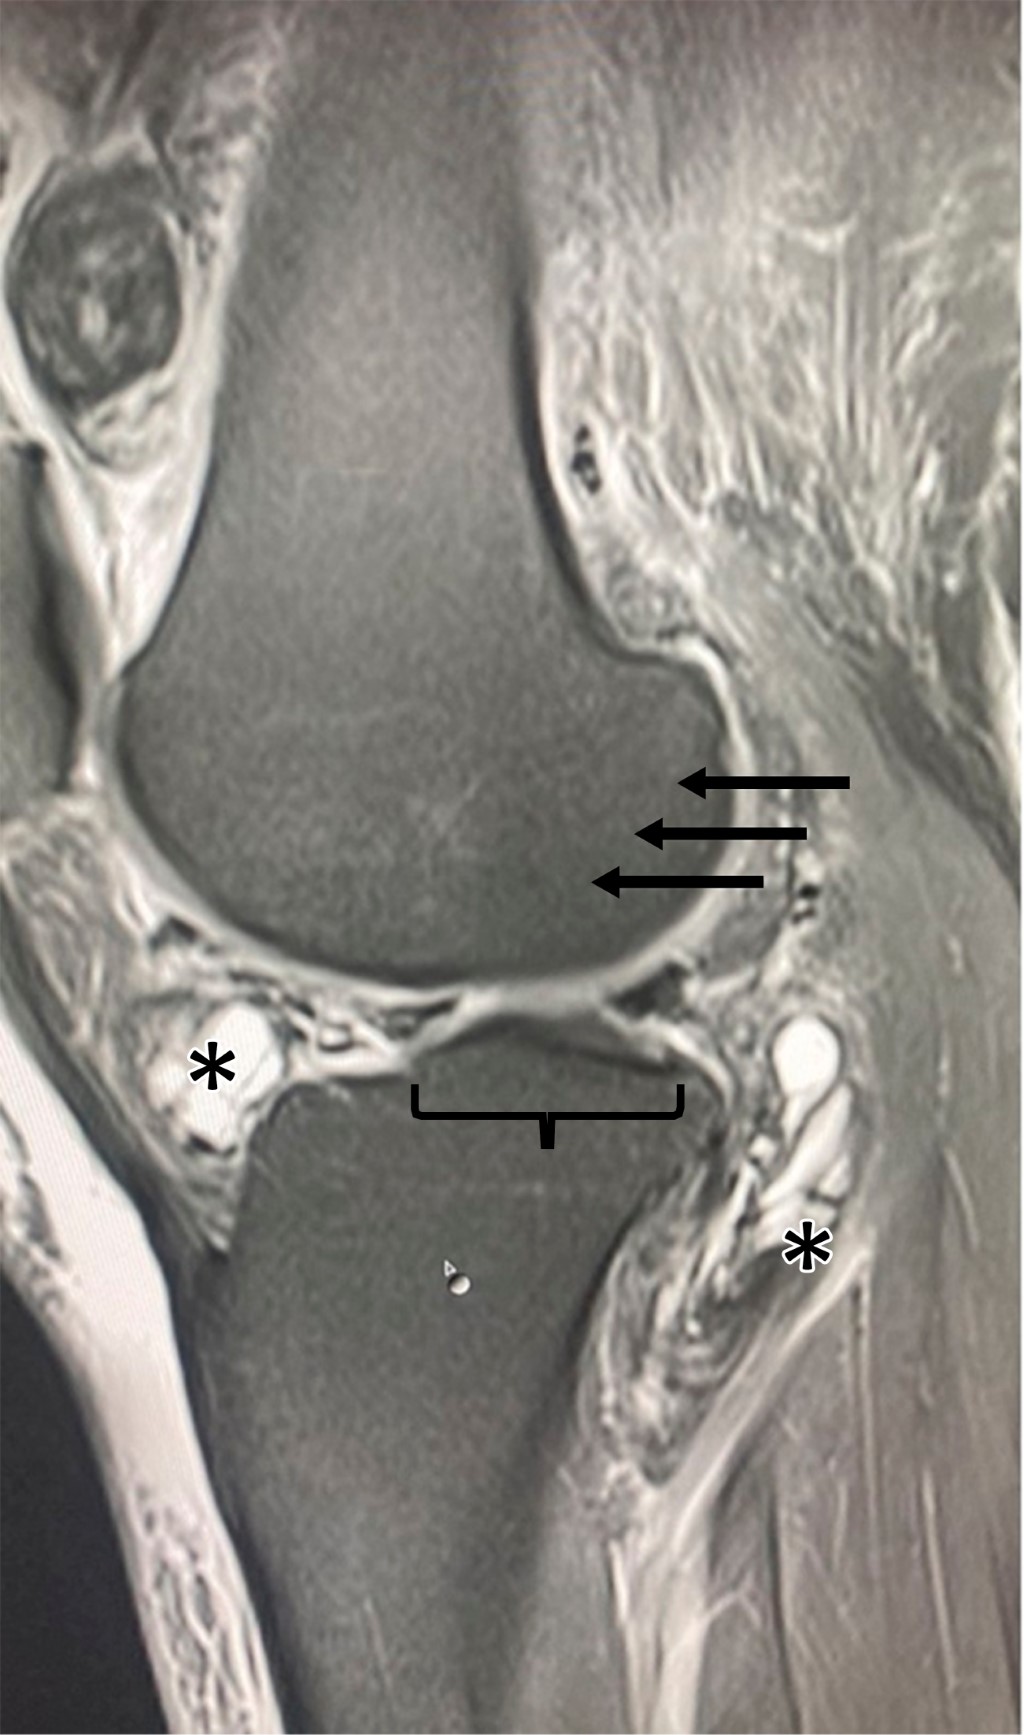

Introduction: pigmented villonodular synovitis (PVNS) is a benign condition that affects the knee, leading to abnormal proliferation of the synovial membrane and the accumulation of hemosiderin in the joint cavity. Although it can be surgically treated, PVNS tends to have a high recurrence rate, potentially resulting in chronic joint damage. Case report: we present the case of a young woman who experienced localized pain in her right knee due to a recurrence of PVNS. Magnetic resonance imaging revealed multiple multilobulated cystic lesions affecting the entire joint, including the ligaments. The patient underwent open surgical resection with a favorable clinical outcome. Histopathological examinations confirmed the absence of malignancy. Conclusion: while arthroscopy is typically the preferred treatment for PVNS, this case highlights the tendency for recurrence associated with this approach. Open surgical resection, supported by benign histopathological findings in this case, suggests a favorable long-term prognosis.

Figure 1